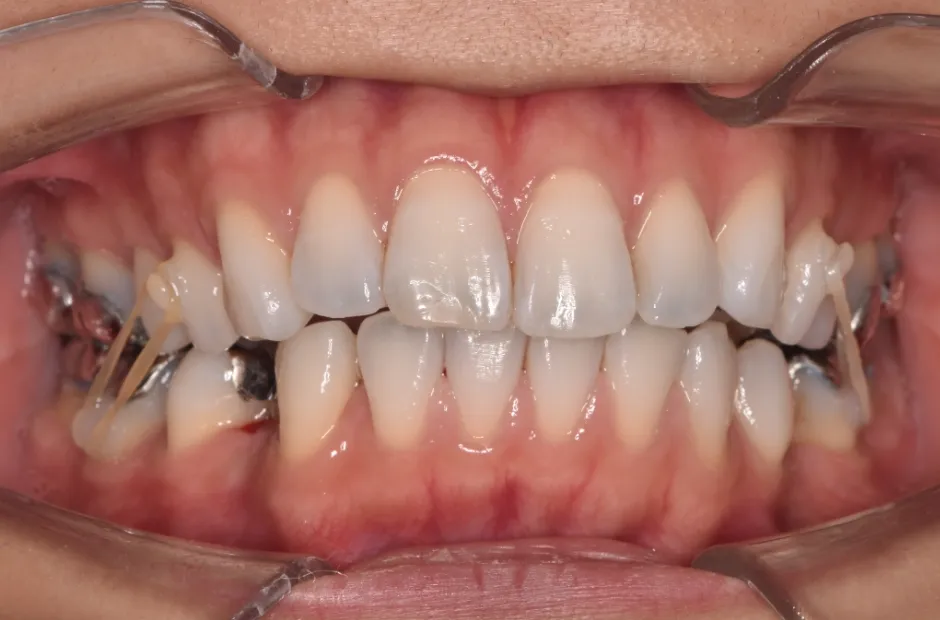

治療中